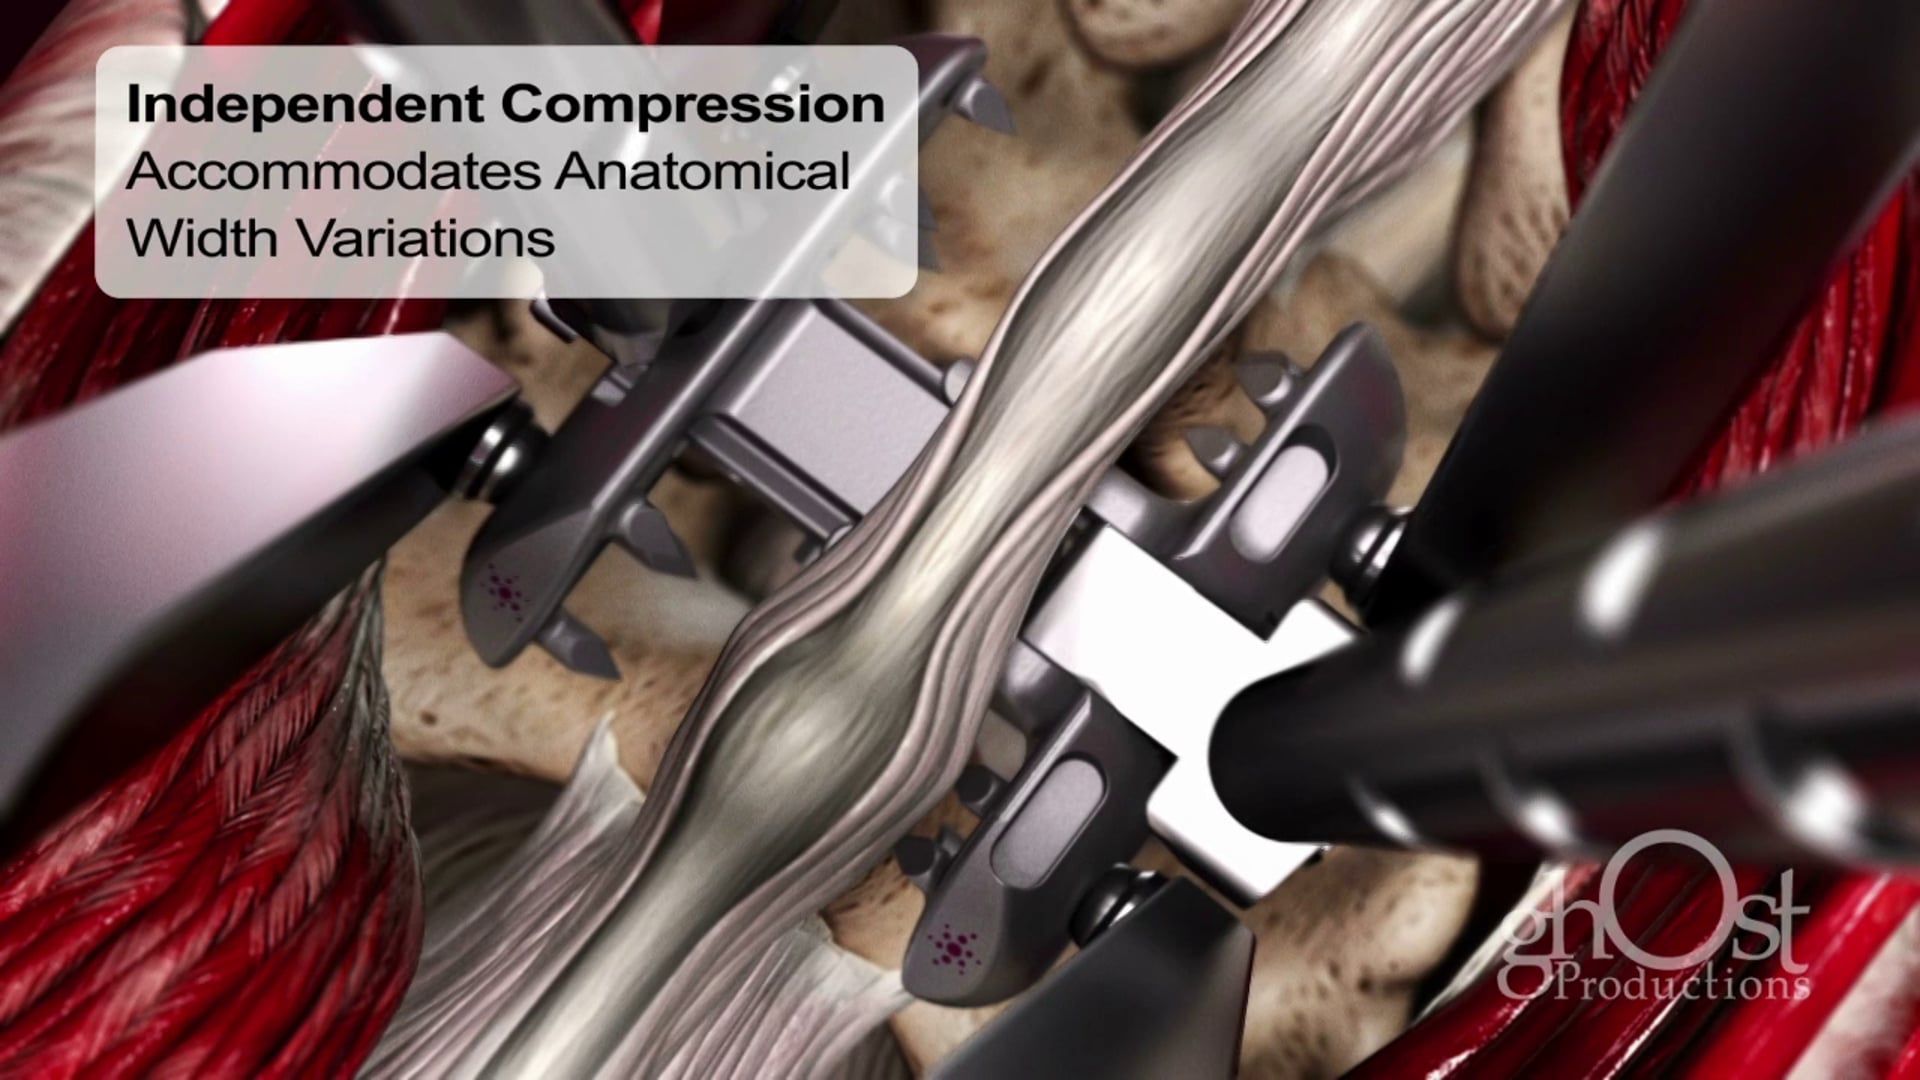

Ghost Productions' animation showcases the Keo Brace, a revolutionary device for Carpal Tunnel Syndrome treatment, providing support to the wrist and reducing pressure on the median nerve. Medically accurate and informative, it's a must-see for healthcare professionals and patients.

Ghost Productions has produced a visually stunning animation that highlights the Keo Brace, a revolutionary device used in the treatment of Carpal Tunnel Syndrome. This video showcases the Keo Brace's unique design and its ability to alleviate the symptoms of Carpal Tunnel Syndrome by providing support to the wrist and reducing pressure on the median nerve. The animation is medically accurate and provides a detailed explanation of how the Keo Brace works, making it an invaluable resource for healthcare professionals and patients alike. This video is a must-see for anyone interested in the latest advancements in the treatment of Carpal Tunnel Syndrome.

Keo Brace, Carpal Tunnel Syndrome, wrist support, median nerve, medical animation, healthcare professionals, patient education, medical device, treatment advancements